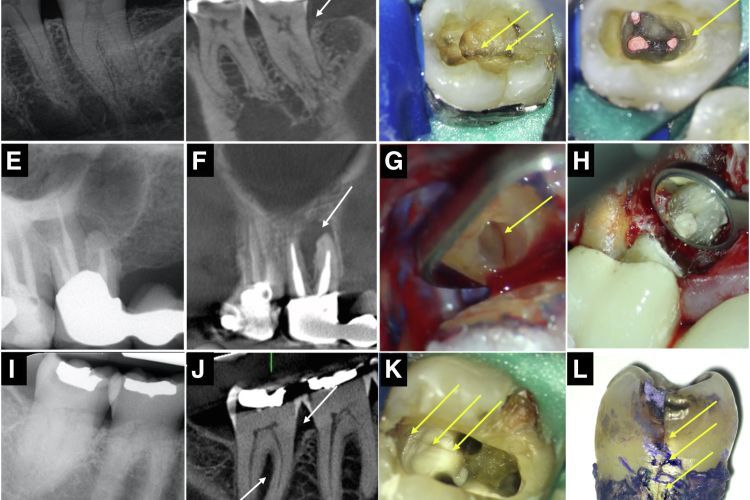

Radiographic presentation of teeth with clinical evidence of longitudinal fractures. (A–D) An angular defect associated with a cracked tooth. (E–H) A J-shaped lesion associated with VRF.

Radiographic presentation of teeth with clinical evidence of longitudinal fractures. (AD) An angular defect associated with a cracked tooth. (EH) A J-shaped lesion associated with VRF.